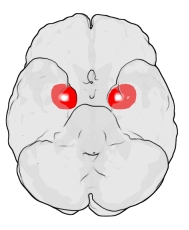

He estado estudiando la amígdala desde hace más de 30 años. Cuando comencé, la investigación […]

Las raíces evolutivas del altruismo humano Los científicos llevan años tratando de identificar el factor […]